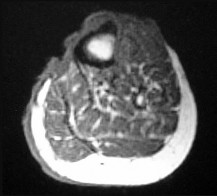

Figures 22a and 22b are the anteroposterior knee radiograph and an axial T2-weighted MR image of an 11-year-old boy who experienced knee pain following soccer practice. What is the best approach for biopsy?

The biopsy should cross only 1 compartment if possible and proceed as directly as possible to the tumor. The lateral parapatellar and medial parapatellar approaches cross the knee joint, potentially visualizing tumor into the knee. A direct anterior approach will contaminate an extensive portion of the quadriceps muscle and potentially complicate limb salvage. Biopsy should be performed at the institution at which definitive resection is planned.